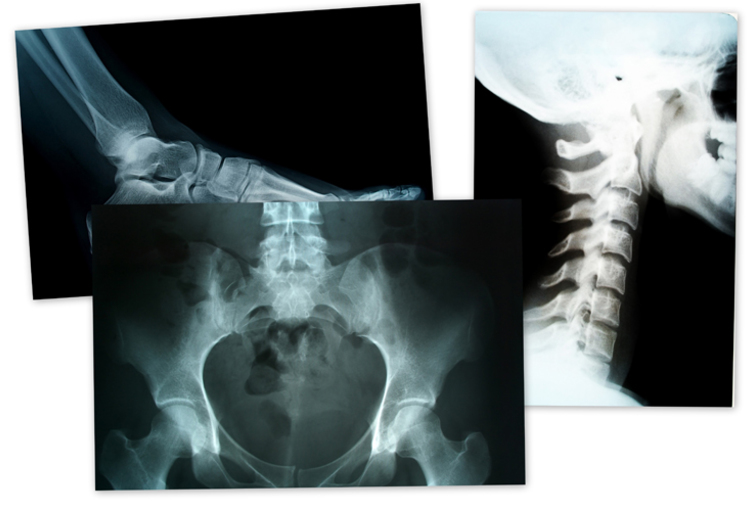

Eerder vorig jaar integreerde het universitair ziekenhuis als eerste zorginstelling in Europa Aidocs oplossing in zijn klinische workflow om twee levensbedreigende pathologieën beter te kunnen opsporen: cervicale wervelfracturen (c-spine) en intracraniële hyperdensiteiten (ICH).

Het UZA kocht de oplossing van Aidoc voor neuroradiologie. Aidoc detecteert acute en levensbedreigende pathologie in CT-scans en duidt die aan zodat de beelden onmiddellijk door een radioloog gezien kunnen worden. Dat resulteert in snellere diagnoses en een kwalitatief betere patiëntenzorg. Het UZA is een van de eerste instellingen in Europa die Aidocs vooruitstrevende technologie toepast.